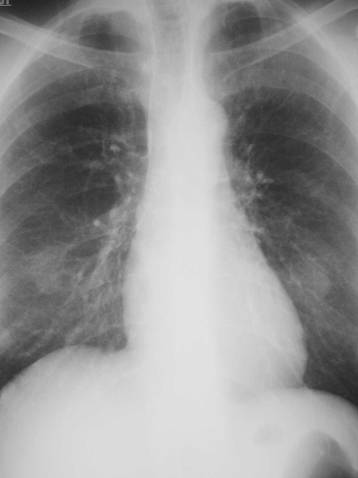

Nipple shadows